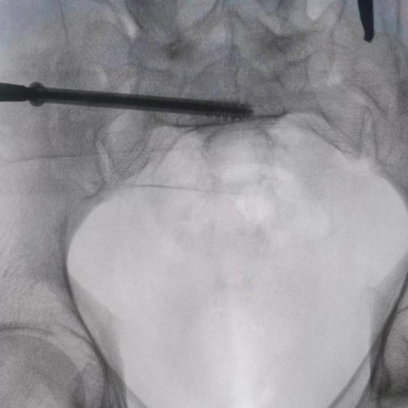

據(jù)了解,患者37歲,為高墜傷患者,入院合并顱腦挫傷、盆腔臟器出血、骨盆骨折多發(fā)傷患者。為最大限度降低手術(shù)風(fēng)險(xiǎn),同時(shí)給予患者滿意的手術(shù)療效,術(shù)前綜合評估患者病情,擬定行“天璣機(jī)器人”輔助定位下骨盆骨折微創(chuàng)手術(shù)。2月13日10時(shí),手術(shù)正式開始。拉薩市人民醫(yī)院采集患者術(shù)中二維影像,通過骨科手術(shù)機(jī)器人擬定螺釘打入位置方向后,吳宏華主任完成手術(shù)設(shè)計(jì),成功為該患者置入了一顆高難度骶髂螺釘,出血5ml,切口1cm。術(shù)后圖像顯示,螺釘位置及方向完全符合手術(shù)規(guī)劃,沒有一絲偏差,手術(shù)最終獲得圓滿成功。

圖為透視下見置入的骶髂螺釘,位置、長度精準(zhǔn),無絲毫偏差